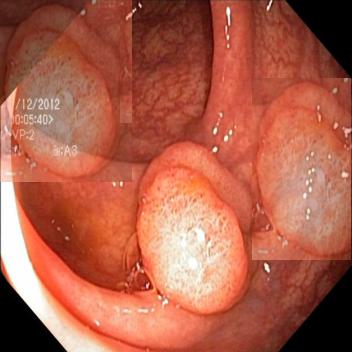

(a) Original Image

(b) GT

(c) Augmented Image

(d) Augmented GT

The pasting module and the update module of the potential map are implemented iteratively 10 times. Thus the foreground area may appear in multiple locations, and an example is depicted in Fig 1.